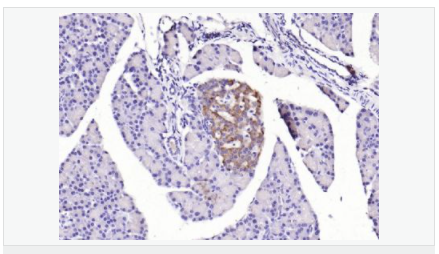

| 產(chǎn)品應(yīng)用 | WB=1:500-2000 ELISA=1:5000-10000 IHC-P=1:100-500 IHC-F=1:100-500 IF=1:100-500 (石蠟切片需做抗原修復(fù)) not yet tested in other applications. optimal dilutions/concentrations should be determined by the end user. |

| 產(chǎn)品介紹 | The protein encoded by this gene is a leucine-rich repeat-containing receptor (LGR) and member of the G protein-coupled, 7-transmembrane receptor (GPCR) superfamily. The encoded protein is a receptor for R-spondins and is involved in the canonical Wnt signaling pathway. This protein plays a role in the formation and maintenance of adult intestinal stem cells during postembryonic development. Several transcript variants encoding different isoforms have been found for this gene. [provided by RefSeq, Sep 2015] Function: Receptor for R-spondins that potentiates the canonical Wnt signaling pathway and acts as a stem cell marker of the intestinal epithelium and the hair follicle. Upon binding to R-spondins (RSPO1, RSPO2, RSPO3 or RSPO4), associates with phosphorylated LRP6 and frizzled receptors that are activated by extracellular Wnt receptors, triggering the canonical Wnt signaling pathway to increase expression of target genes. In contrast to classical G-protein coupled receptors, does not activate heterotrimeric G-proteins to transduce the signal. Involved in the development and/or maintenance of the adult intestinal stem cells during postembryonic development. Subunit: Identified in a complex composed of RNF43, LGR5 and RSPO1. Subcellular Location: Cell membrane; Multi-pass membrane protein Tissue Specificity: Expressed in skeletal muscle, placenta, spinal cord, and various region of brain. Expressed at the base of crypts in colonic and small mucosa stem cells. In premalignant cancer expression is not restricted to the cript base. Overexpressed in cancers of the ovary, colon and liver. Similarity: Belongs to the G-protein coupled receptor 1 family. Contains 16 LRR (leucine-rich) repeats. Contains 1 LRRNT domain. SWISS: O75473 Gene ID: 8549 Database links: Entrez Gene: 8549 Human Entrez Gene: 14160 Mouse Omim: 606667 Human SwissProt: O75473 Human SwissProt: Q9Z1P4 Mouse Unigene: 658889 Human Unigene: 42103 Mouse Unigene: 214063 Rat Important Note: This product as supplied is intended for research use only, not for use in human, therapeutic or diagnostic applications. Lgr5基因(Wnt細(xì)胞信號系統(tǒng))是一種G蛋白偶聯(lián)受體,已經(jīng)被確定為幾種成年組織和癌癥中干細(xì)胞的一個(gè)獨(dú)特標(biāo)記。Lgr5最初是在結(jié)腸癌細(xì)胞中發(fā)現(xiàn)的,有報(bào)道稱:在惡化前的小鼠腺瘤中也有發(fā)現(xiàn),這說明Lgr5很可能也是其他組織成體干細(xì)胞和癌癥干細(xì)胞的標(biāo)志物。 |